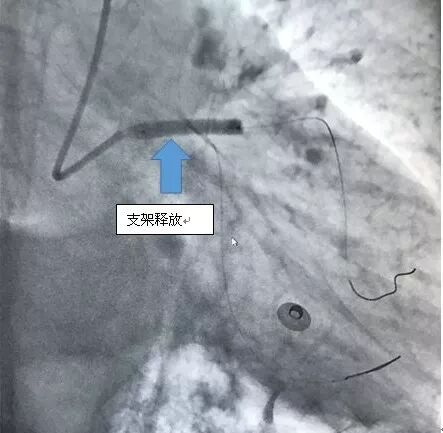

下午4点手术开始,造影显示李爹爹左主干严重狭窄 90%以上,命悬一线。在向病人家属交代病情后,王祥教授带领黄仲略主任和苏华俊主任迅速为患者植入支架,打通血管。血管打通仅花了20分钟。